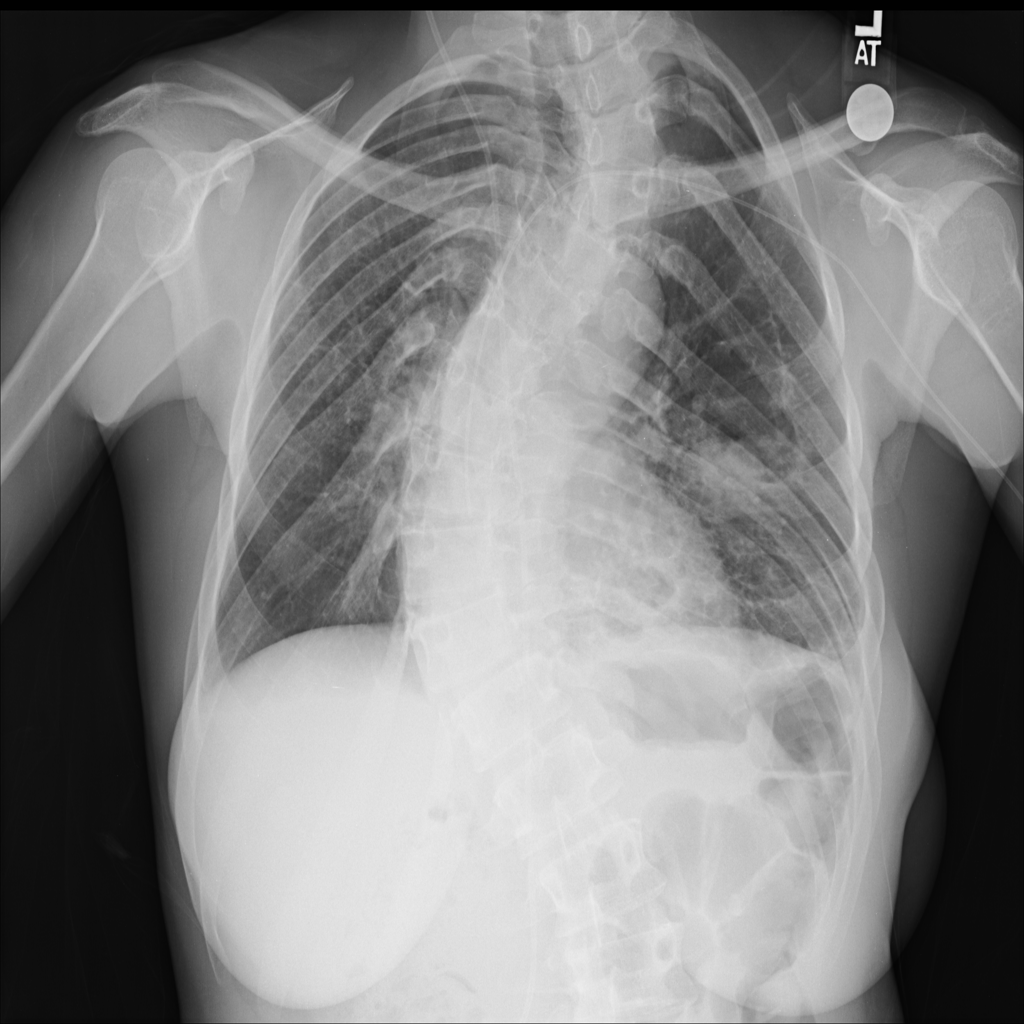

Nodule

A nodule is a small rounded opacity in the lung or chest field. It is a descriptive imaging finding that can be benign or more concerning depending on size, appearance, and context.

Showing up to 90 reference images for Nodule.

PAT-250B · IMG-000Nodule

PAT-250B · IMG-000

PA